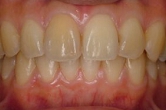

↓前歯の歯並びを きれいに治したい。

(35歳/女性)

概要・担当医コメント:叢生・審美障害↑

動的治療期間13ヶ月(12回)/非抜歯/費用概算:55万円

上は固定式のブラケット矯正で,下は患者様ご自身が着脱するマウスピース矯正の治療を行いました.治療結果には大変満足されているそうです.